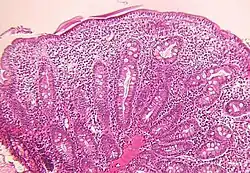

Small intestine biopsy of a patient with THE syndrome showing severe villous atrophy with intense mononuclear cell infiltration in the lamina propria. (Courtesy of Prof. Michel Peuchmaur, Hôpital Robert Debré, Paris, France)

Microscopic examination of a biopsy of the small bowel in these patients shows villous atrophy with low or no mononuclear cell infiltration of the lamina propria nor specific abnormalities involving the epithelium. The amount of villous atrophy does not explain the severity of the diarrhea.